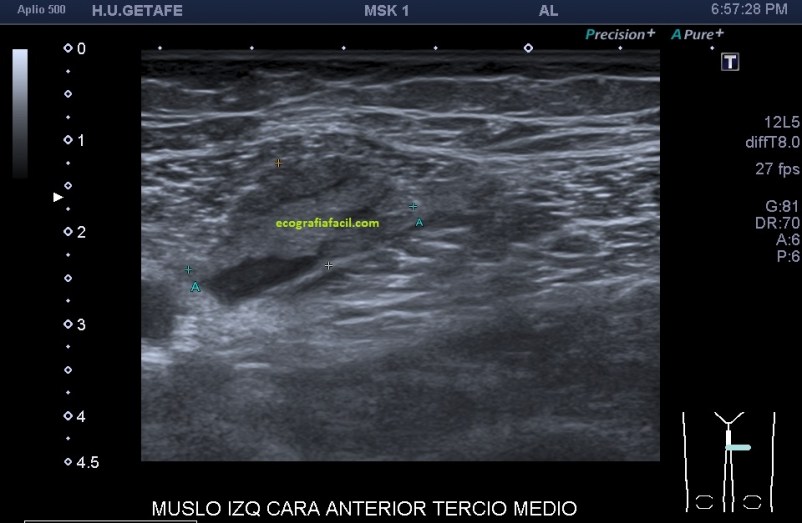

Después de estudiar la rotura en dos planos (imagen 1 y 2) y medirla (imagen 3 y 4), documentarla bien referenciándola con la anatomía locorregional, incluidos los vasos (imagen 5), decidí seguir el recorrido del músculo partiendo desde la rotura siguiendo las instrucciones que me había comentado la paciente y me dí cuenta que el músculo afectado cruzaba el muslo desde el tercio proximal del muslo, en la cara anterior de la cadera (en su porción más superficial) hasta la cara interna de la pierna…en concreto desde la espina iliaca antero superior y terminando en la inserción de la Pata de Ganso.

Eje largo, con la anatomía de referencia. Observamos las fibras alargadas, rodeadas por el líquido y el abombamiento producido por el sangrado.

Medidas en eje largo